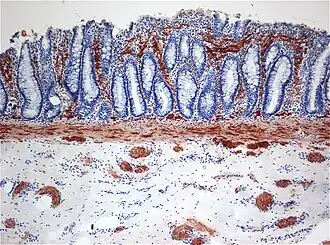

De diagnose kan gesteld worden door middel van het uitvoeren van een biopsie van het rectum (rectumzuigbiopt). Dit is momenteel de gouden standaard voor de diagnose van de ziekte van Hirschsprung.[20] Hierbij wordt een stukje weefsel uit het rectum genomen dat vervolgens wordt onderzocht op de aanwezigheid van ganglioncellen en zenuwbundelproliferatie. Dit onderzoek kan aangevuld worden met een anorectale manometrie en een coloninloopfoto indien er nog twijfel bestaat over de diagnose. Wanneer deze drie onderzoeken nog steeds geen duidelijkheid hebben verschaft kan een full-thicknes-biopt worden verricht.[21] Hierbij wordt meer weefsel verkregen dan bij een rectumzuigbiopt met daardoor een betrouwbaardere uitslag. Tevens zijn hier wel meer risico’s aan verbonden.